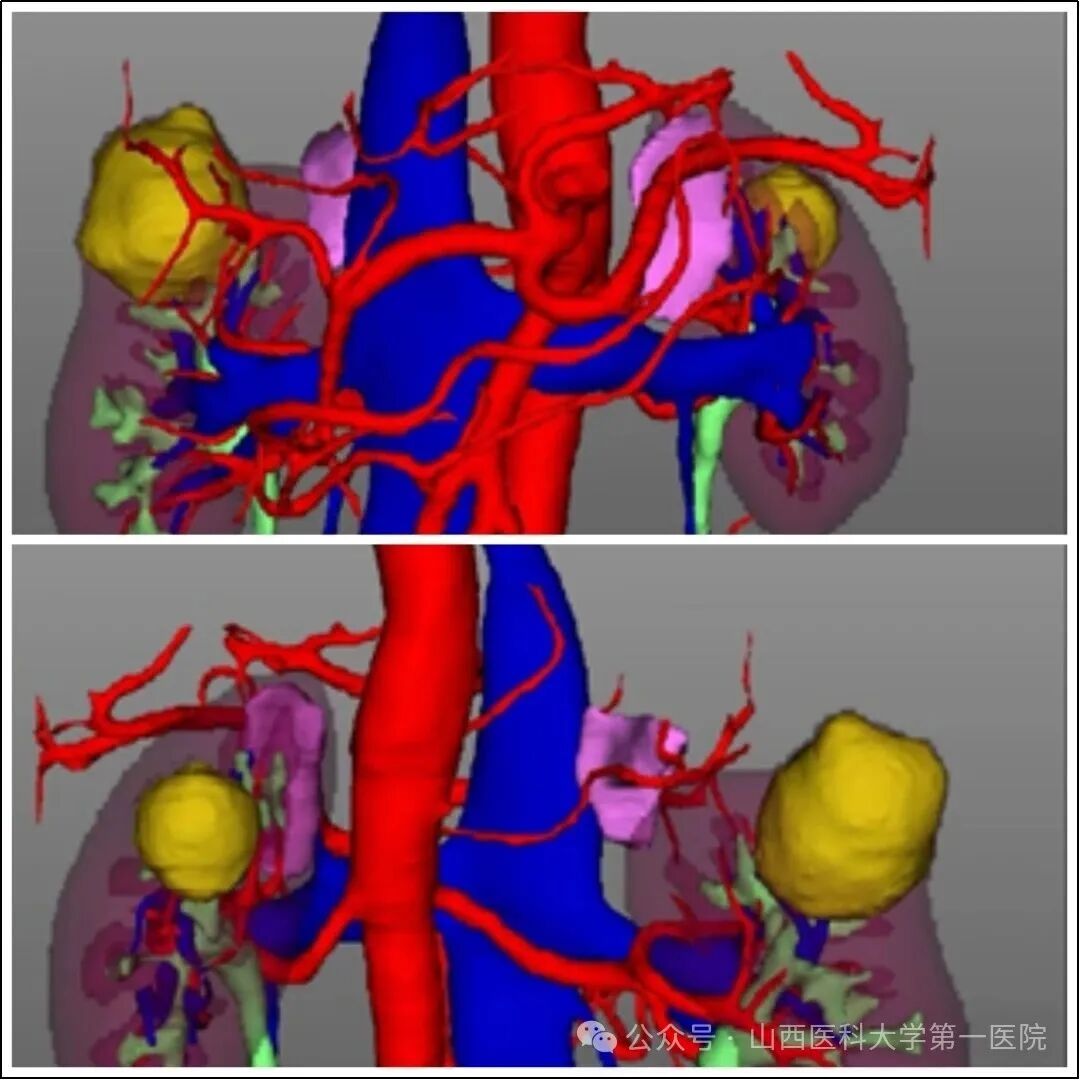

术前三维数字重建正面观及背面观,图中黄色包块即为肾肿瘤